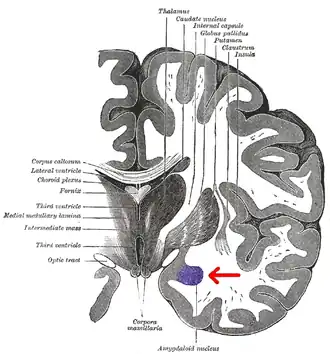

Миндалевидное тело (лат. corpus amygdaloideum), ами́гдала[1] — область мозга миндалевидной формы, находящаяся в белом веществе височной доли полушария под скорлупой, примерно на 1,5—2,0 см сзади от височного полюса. В мозге два миндалевидных тела — по одному в каждом полушарии[2]. Миндалевидное тело играет ключевую роль в формировании эмоций, в частности, страха. У пациента, миндалевидное тело которого оказалось полностью разрушено вследствие болезни Урбаха — Вите, наблюдалось отсутствие страха[3][4][5]. Миндалевидное тело также играет важную роль в функционировании памяти, принятии решений и эмоциональных реакциях[6]. Миндалевидное тело является частью лимбической системы, относится к подкорковым обонятельным центрам.

Области мозга, называемые миндалевидными ядрами, включают несколько структур со схожими функциональными характеристиками у человека и животных[7]. В число этих структур входит базолатеральный комплекс, ядра коры, срединное ядро, центральное ядро и клетки интерстиция. Базолатеральный комплекс, в свою очередь, делится на латеральное, базальное и добавочное ядра[6][8][9]. Анатомически миндалевидное тело[10], в частности, его центральное и медиальное ядра[11], иногда включаются в состав базальных ганглиев.